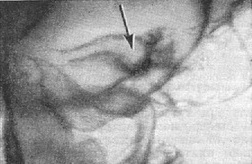

Вивчення їх стану нерідко вимагає застосування спеціальних двухмоментных проекцій для зіставлення однойменних деталей правої і лівої сторін. Іноді незначна деструкція або відносно невелике розширення одного з каналів може вказувати на наявність пухлини відповідного нерва (див. Головний мозок, рентгенодіагностика захворювань). Так, наприклад, при глиоме зорового нерва обов'язково дослідження в проекції Резе - Голвина (рис. 4), а при невриномі VIII нерва, розширює внутрішній слуховий прохід,- проекції пірамід по Стенверсу (рис. 14).

![]() Рис. 14. Невринома правого слухового нерва. Рентгенограма пірамід скроневих кісток по Стенверсу. Праворуч визначається різке розширення внутрішнього слухового проходу. Рис. 15 (праворуч). Гострий синуит. Рентгенограма придаткових пазух носа. Вертикальне положення голови хворого і касети. Видно горизонтальні рівні рідини в правій лобовій і правої гайморової пазусі. |